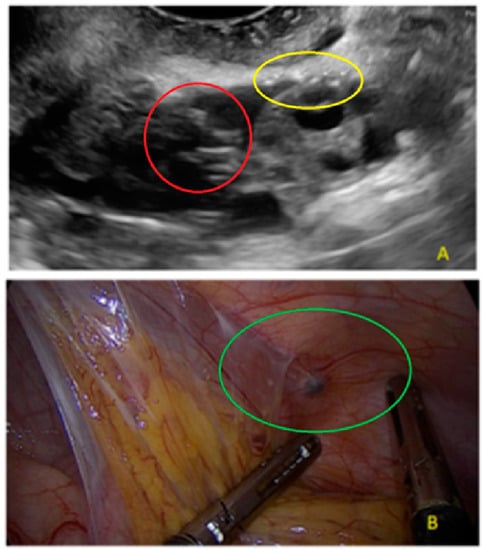

3.2. Cystic Multiple Separate Lesions

- The lesion may be convex, protruding from the peritoneal surface into the peritoneal cavity (we called this “bulging”), or it may appear as a concave defect in the peritoneum (we called this a “pocket”).